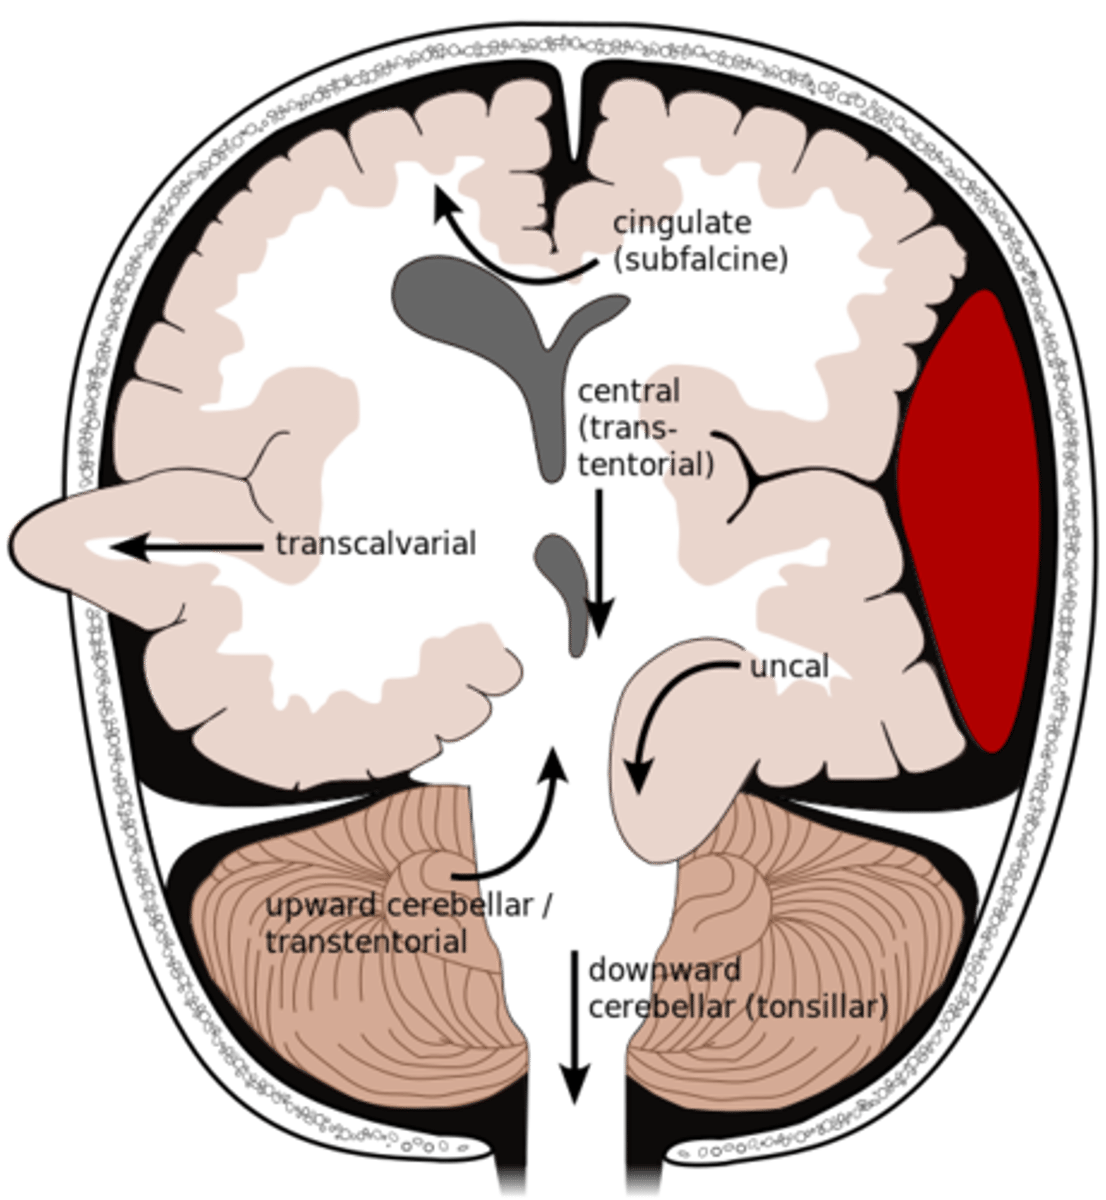

What is an uncal herniation?

most common.

unilateral lesions forces uncus of temporal lobe to displace and compress on the midbrain.

What is a central herniation?

Downward shift of cerebral hemisphere, compressing the brainstem

What is a cingulate herniation?

shift of brain tissue from one hemisphere to the other. Compress anterior cerebral artery.

Ischemic stroke may occur

What is a transcalvarian herniation?

brain begins to herniate outside of the skull. the brain will squeeze out of fractures, burr holes, or surgical incisions.

What is an upward herniation?

displacement of the cerebellum upward

What is a cerebellar Tonsillar herniation?

displacement of cerebellar tonsils downward this compressing the pons/medulla

s/s: alterations in resp. and cardiac functions- rapidly progressing to cardiac arrest, Headache and neck stiffness, reduced muscle tone